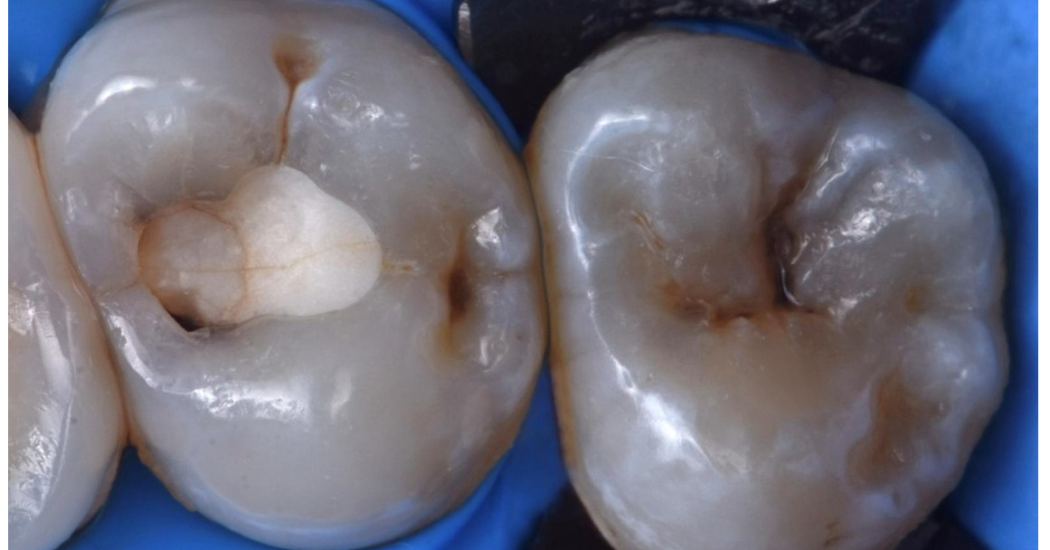

In questo caso clinico, il Dr. Tosco (Italia) spiega come sfrutta le proprietà terapeutiche e restaurative di Biodentine™ XP per trattare due denti affetti da lesioni cariose profonde, con l’obiettivo principale di preservare la vitalità pulpare e mantenere l’integrità strutturale degli elementi dentali.

Mantenere la vitalità pulpare è un obiettivo fondamentale nell’odontoiatria restaurativa, in particolare nei pazienti giovani, dove le lesioni cariose profonde possono progredire rapidamente. In questi casi, l’incappucciamento pulpare indiretto rappresenta un approccio prezioso per preservare la polpa evitando ulteriori compromissioni strutturali.» – Dr. Vincenzo Tosco ”